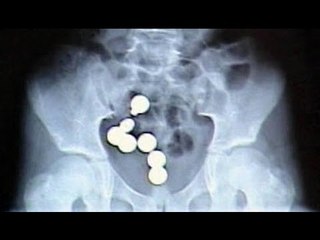

Police: Notre Dame Prep student arrested for having fentanyl pills

Scottsdale police and firefighters responded to an overdose call around 11:20 p.m. on February 6.